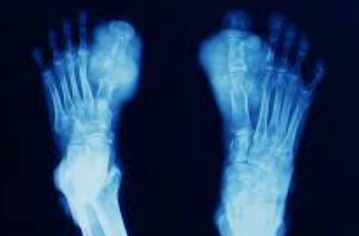

통풍은 일반적으로 한 번에 하나의 관절에 영향을 미치며 가장 일반적으로 엄지발가락에 영향을 미칩니다. 그러나 발목, 무릎, 팔꿈치, 손목 및 손가락과 같은 다른 관절에도 영향을 줄 수 있습니다. 통풍 증상은 보통 밤에 발생하며 종종 사람들을 잠에서 깨게 하며 중간 정도의 불편함에서 심한 통증에 이르기까지 다양합니다. 다음은 통풍 증상과 관련된 몇 가지 주요 내용입니다.

1. 심한 관절통: 통풍은 보통 한 번에 한 관절에 영향을 미치며 종종 엄지발가락 관절에서 시작됩니다. 통증은 일반적으로 시작된 후 처음 4~12시간 이내에 가장 심한 통풍 증상이 나타납니다.

3. 염증 및 발적: 영향을 받은 관절이 부어오르고, 압통이 생기고, 따뜻해지고, 붉어집니다.

4. 운동 범위 제한: 통풍이 진행됨에 따라 관절을 정상적으로 움직이지 못할 수 있습니다.